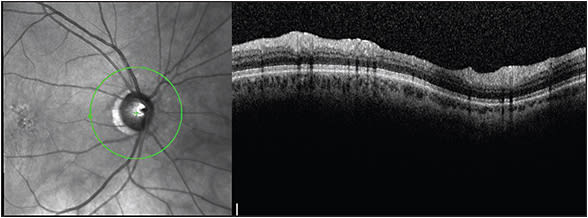

A 56-year-old patient presented with new floaters in both eyes. The exam was difficult, and a Weiss ring could not be visualized in either eye. The OCT imaging showed PVD in the right eye (Figure 3) but not in left (Figure 4), which meant that the lack of a Weiss ring visualization was due to the exam difficulty in the right eye while in the left eye it was because the vitreous was not yet completely separated. The patient was advised accordingly.